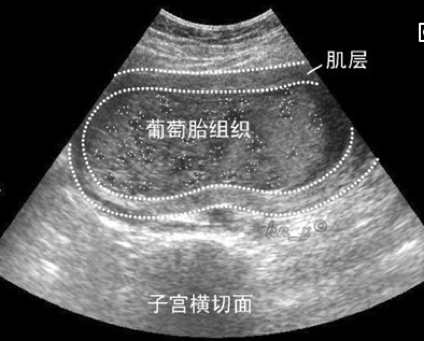

(1)肉眼观,病变局限于宫腔内,不侵入肌层。胎盘绒毛高度水肿,形成透明或半透明的薄壁水泡,内含清亮液体,有蒂相连,形似葡萄。若所有绒毛均呈葡萄状,称之为完全性葡萄胎;部分绒毛呈葡萄状,仍保留部分正常绒毛,伴有或不伴有胎儿或其附属器官者,称为不完全性或部分性葡萄胎。绝大多数葡萄胎发生于子宫内,个别病例也可发生在子宫外异位妊娠的所在部位。

(2)镜下,葡萄胎有以下三个特点:①绒毛因间质高度水肿而增大;②绒毛间质内血管消失,或见少量无功能的毛细血管,内无红细胞;③滋养层细胞有不同程度增生,增生的细胞包括合体细胞滋养层细胞(syncytiotrophblast)和细胞滋养层细胞(cytotrophoblast),两者以不同比例混合存在,并有轻度异型性。滋养层细胞增生为葡萄胎的最重要的特征。

患者多半在妊娠的第四或第五个月出现症状,由于胎盘绒毛水肿致子宫体积明显增大,超出相应月份正常妊娠子宫大小。因胚胎早期死亡,虽然子宫超过5个月妊娠大小,但仍听不到胎心,亦无胎动。由于滋养细胞增生,患者血和尿中绒毛膜促性腺激素(Human chorionic gonadotropin,HCG)明显增高,是协助诊断的重要指标。滋养层细胞侵袭血管能力很强,故子宫反复不规则流血,偶有葡萄状物流出。如疑为葡萄胎时,大多数患者可经超声检查确诊。